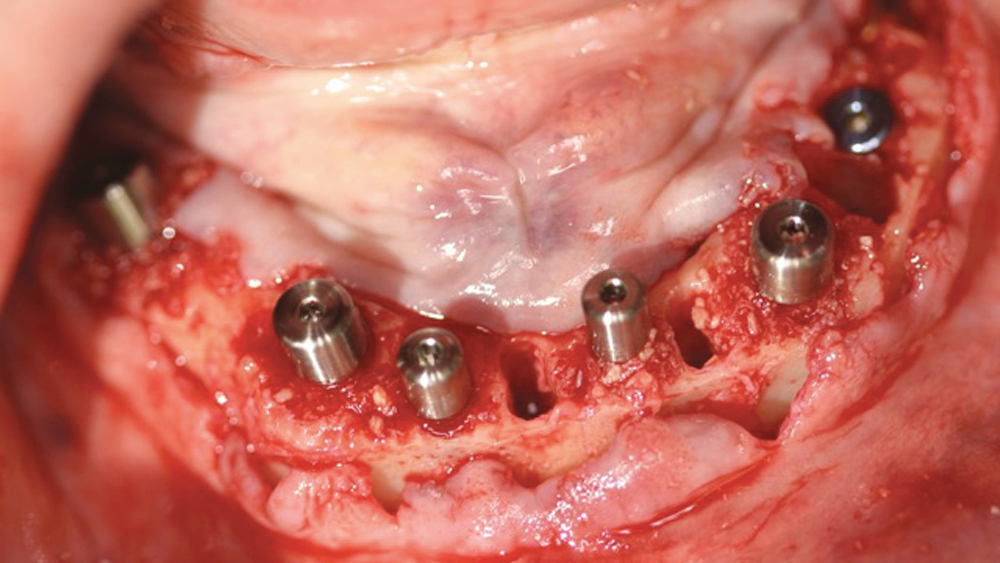

To establish the foundation needed for a screw-retained restoration and avoid fracturing the facial plate, clinicians must position the immediately placed implant against the lingual or palatal wall of the extraction socket. This is one of the reasons I designed the Hahn™ Tapered Implant (Glidewell Direct; Irvine, Calif.) with deep, sharp threads, which enable precise directional control during insertion and prevent the implant from “walking” toward the facial plate as it is threaded into place. This thread design also leads to high primary stability in all bone types, which is essential when performing the extraction with immediate implant placement procedure.1,2

The following case demonstrates how to immediately place implants in full-arch indications. By properly positioning the implants, maximizing primary stability and providing the most durable restoration possible, the short- and long-term needs of the patient are addressed in an efficient, predictable manner.